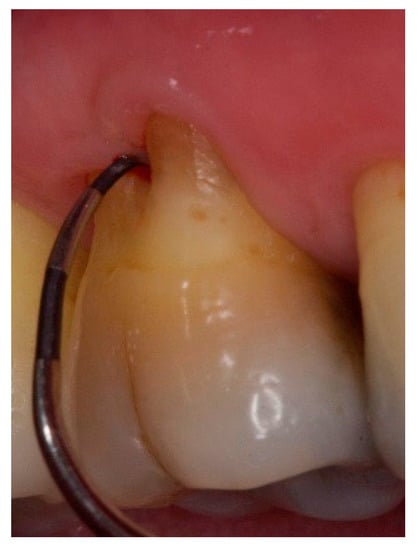

Figure 8. Exposed furcation lesion—Class II (EII): First maxillary molar. Buccal furcation lesion with horizontal attachment loss of 4 mm.